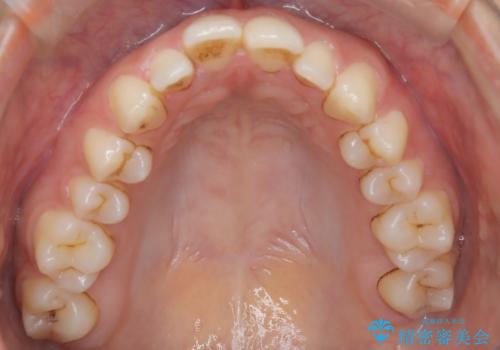

- 患者様は、前歯が出ている状態(上顎前突)と隙間を閉じたいというご希望で来院されました。診断の結果、骨格性の上顎前突が確認されたため、理想的には外科矯正が必要であることを説明しましたが、患者様の「非抜歯でできる範囲で治療を進めたい」という希望を尊重し、矯正治療計画を立てました。治療目標は、前歯の突出を可能な限り改善し、隙間を閉じることに重点を置きました。

本症例では、非抜歯での治療を選択したため、スペースを確保するためにIPR(歯間削合)を行い、歯列を整えました。オーバージェット(上の前歯と下の前歯の水平的なズレ)は残る結果となりましたが、見た目や機能の改善を重視し、患者様と治療計画を共有しながら進めました。治療中は、歯列全体のバランスと噛み合わせを考慮しつつ、矯正装置の適切な使用を徹底しました。当初の計画通りに治療を完了し、患者様にも満足していただけました。